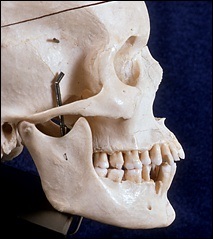

A téma ez a fejezet - acanthion. Acanthion - ez terjed ki előre a csontképződést, található az alapja az orr. A jobb felső fotó rajta a sárga nyíl.

A fenti képek acanthion nagyon kis méretű. Valószínűleg ez része a csont megtört sok éve létezik a koponya. Ez a fejezet fog beszélni, amikor az orr gerinc nagyobb a szükségesnél.

Mielőtt nagyobb acanthion. Ez az, amit úgy néz ki, a művelet során. Az ábrán a jobb ez sárga színű. Acanthion columella található, közvetlenül alatta, ahol a felső ajak határos az alapja az orrát.

A jobb felső sarokban a kép jól látható acanthion (sárga színnel jelöltek). Az alsó képen az azonos, de a távoli nazális gerinc.